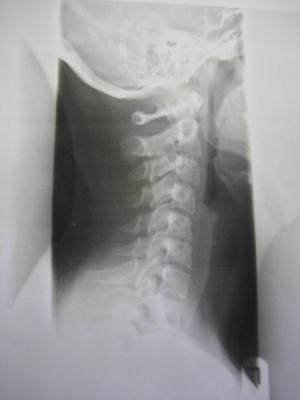

Heute war ich hier beim Durchgangsarzt,da momentan alle Orthopäden hier Urlaub haben bis nach Ostern und ich Probleme habe meinen Kopf vernünftig zu bewegen.Er hat Röntgenbilder gemacht und ich hab einen richtigen Schock bekommen.Das was ich vermutet habe,hat sich wohl bestätigt,es ist schlimmer geworden mit der Skoliose und ich muss sofort zu einem Orthopäden.Ich habe stärkere Schmerzmittel bekommen und mein Arzt meint,ich brauche wohl ein Korsett.....

Ich hab mal die Bilder vom Röntgen angehängt.Den Grad der Verkrümmung weiss ich leider noch nicht.Aber kann mir vielleicht jemand was zu den Bildern sagen?